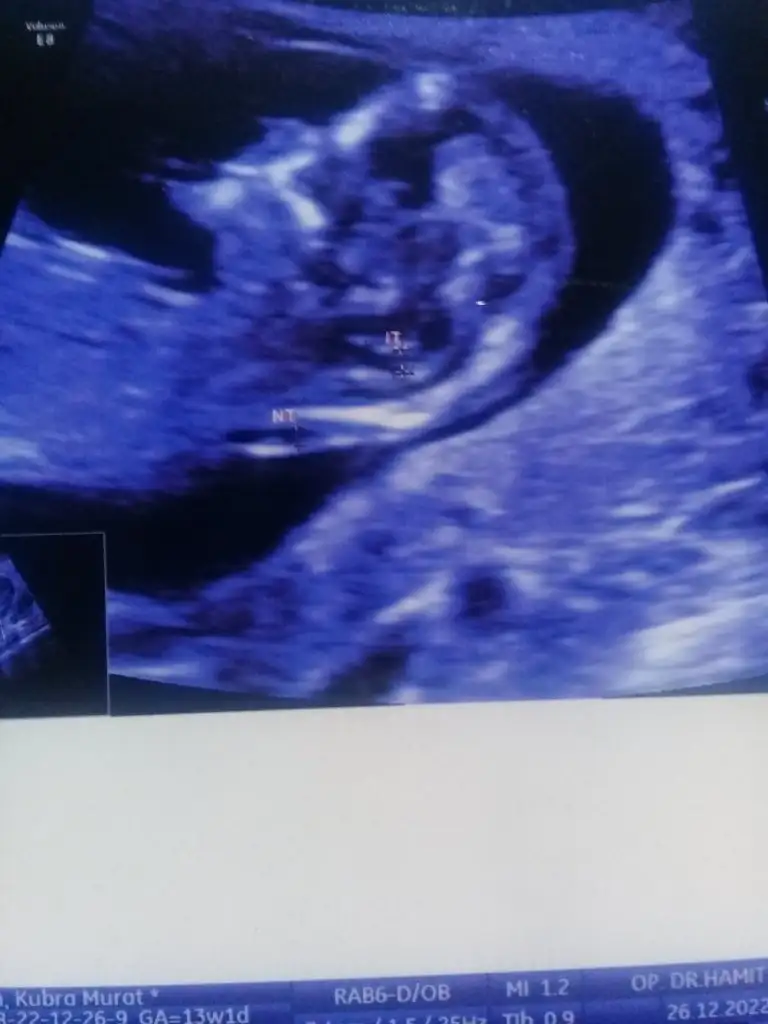

Kızlar 13+4 haftalıkken doktor çok kararsız kaldı ama kıza benziyor dedi hazırlık yapma dedi ben erkek hissediyorum bana da bakabilir misiniz?

Eklentiler

• EA664CFF-9DB4-4DB5-8368-050F621E4192.webp

EA664CFF-9DB4-4DB5-8368-050F621E4192.webp

25,7 KB · Görüntüleme: 484

Bu cuma tekrar gitcem erkek derlerse gine erkektir büyük ihtimal ama ayrintiliya girmek isterim öyle daha net olur